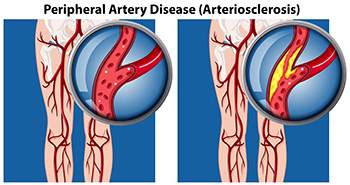

Buerger Disease

Buerger Disease Buerger disease is a condition where the small and medium blood vessels in the arms and legs become inflamed and blocked, resulting in vasculitis. The blood flow is reduced to the affected areas of the body and tissue damage can ensue. Symptoms of this...